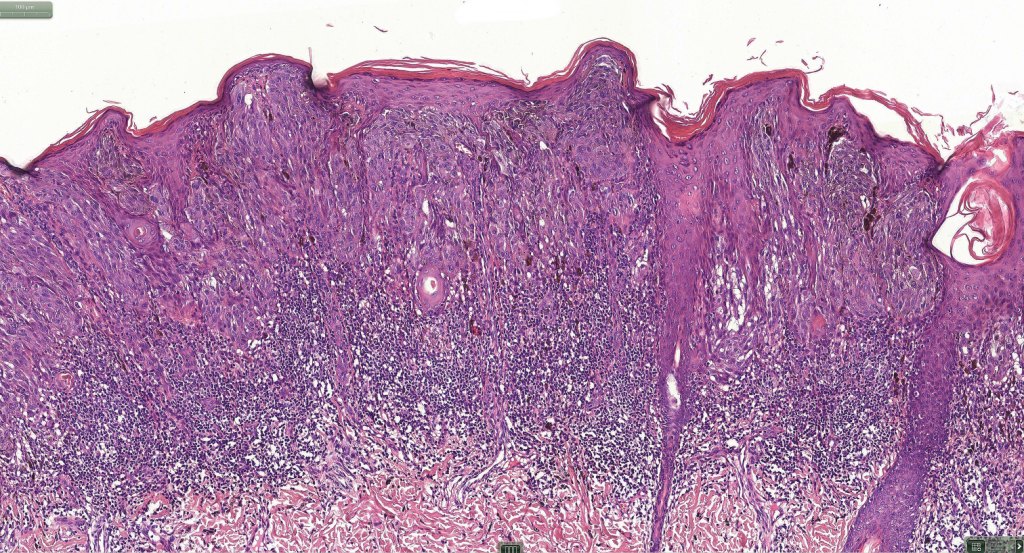

•Sharply circumscribed (begins and ends with a nest), symmetrical dome-shaped lesion. Symmetry is both horizontal and vertical (see image below)

•Wedge-shaped with the base uppermost or sometimes plaque-shaped silhouette

•Matures with depth-often best recognized at scanning/low power magnification & readily confirmed with S100 or MART1

•Maturation implies nest size and cell size diminishing with depth, at the base, the infiltrate may have a single cell infiltrating pattern

•Hyperkeratosis & acanthosis, sometimes very marked

•Junctional nests often vertically orientated, dyscohesive with a surrounding retraction artifact

•Lymphocytic infiltration at the base of the lesion